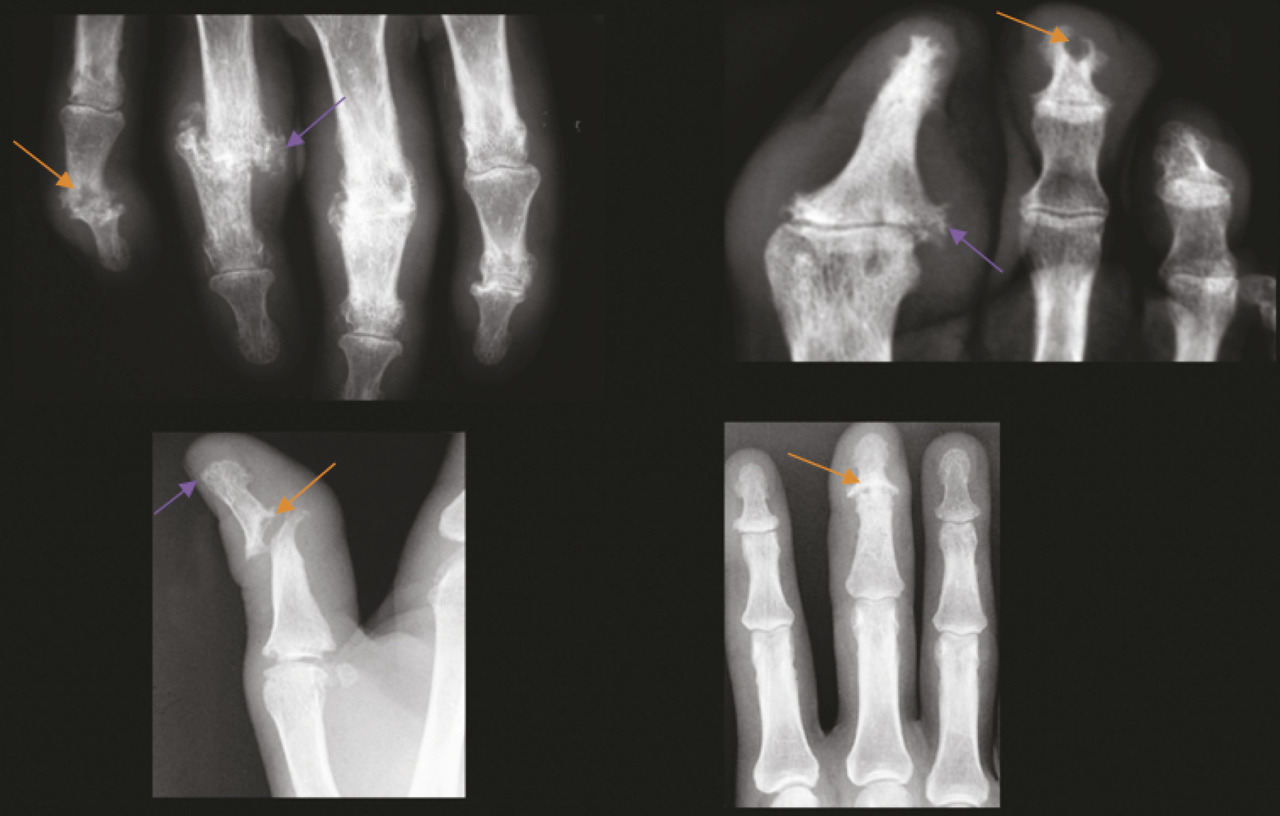

L’atteinte périphérique est également polymorphe, avec des arthralgies simples, des oligoarthrites asymétriques, des dactylites mais aussi parfois de véritables tableaux de polyarthrites érosives et mutilantes. Dans ces dernières, on observe l’association de lésions constructrices (ankylose, périostose, syndesmophytes) et de lésions destructrices (érosions, acro-ostéolyse) sur une même arti- culation ou une même région ana- tomique (main, pied) [v. figure]. Le pronostic fonctionnel dépend de l’activité de la maladie et des destructions structurales responsables du handicap.